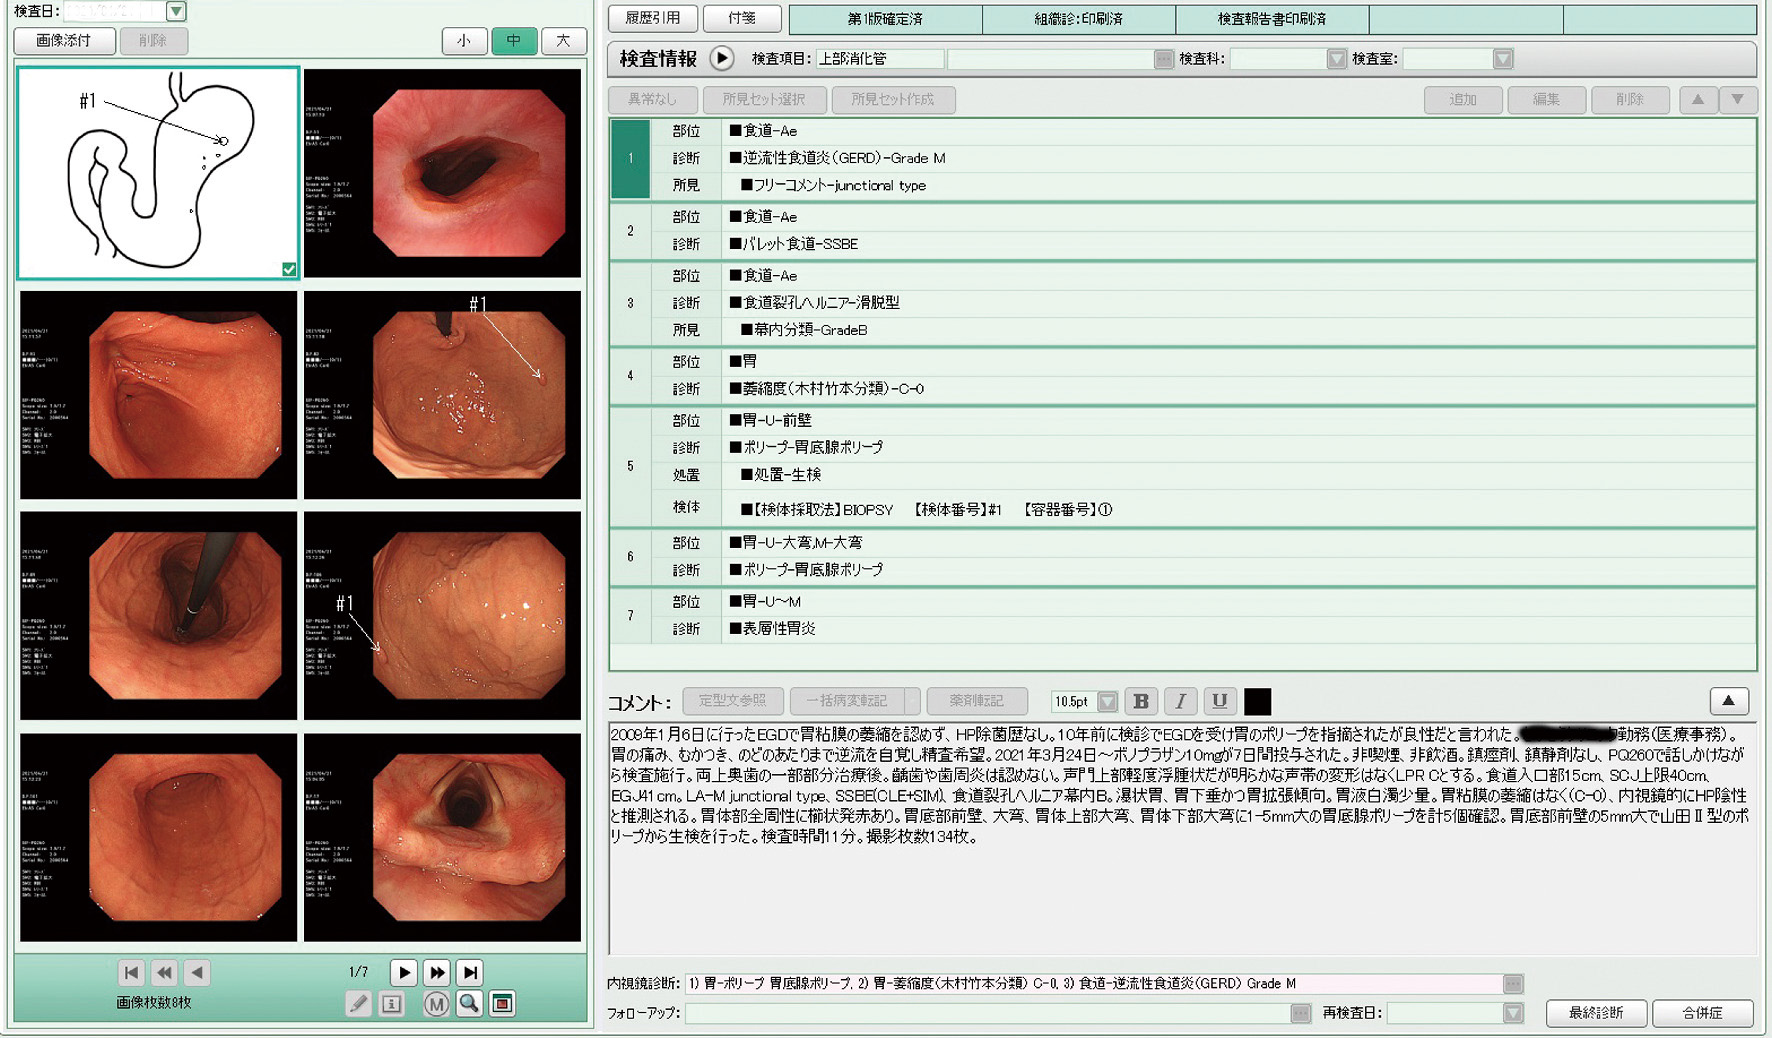

【症例3】80歳代,女性.

主訴:咽頭違和感,呑酸,げっぷ,前屈時の胸やけ (Fスケール7点)

既往歴など:強皮症 (limited type).H. pyloriの除菌歴なし.非喫煙,習慣飲酒 (赤ワイン1~2杯/日).

悪性腫瘍の家族歴:なし

内服歴:ファモチジン20 mg,サルポグレラート塩酸塩3錠/日.

内視鏡検査法:鎮痙剤・鎮静剤なし,炭酸ガス送気使用,経口挿入.IEE (BLI,LCI併用).

使用機種:EG–L580NW7 (富士フイルム,原色カラーフィルター同時方式電子内視鏡)

検査場所:獨協医科大学病院 (栃木県下都賀郡)

内視鏡画像:ⓔ動画11-1-6 (122枚の静止画を連続再生)

内視鏡検査所見・report (図3) 参照

内視鏡検査ビデオ:ⓔ動画11-1-7参照

検査時間:14分

撮影枚数:122枚

生検結果:なし